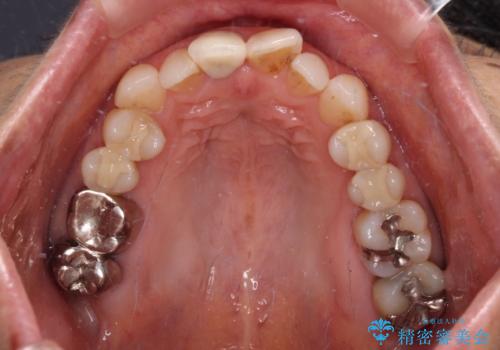

- 前歯のデコボコと口を開けたときに見える銀歯を気にして来院された患者様です。

矯正治療後に銀歯をセラミッククラウンなどに置き換えていくと、どうしても後戻りを起こしてしまうため、矯正治療が概ね終了した時点で銀歯を全てセラミックとし、最後に仕上げでインビザラインにを用いて細かいデコボコを改善していくこととしました。